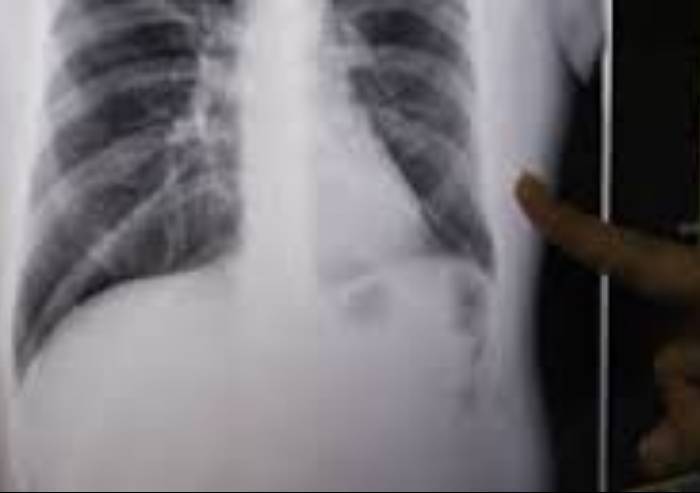

Un caso di tubercolosi in un giovane residente a Modena è stato segnalato al Servizio igiene pubblica dell’Azienda Usl. Come previsto dai protocolli delle malattie infettive, l'Azienda Usl ha individuato i contatti e avviato le procedure previste per lo svolgimento degli accertamenti necessari e la sorveglianza sanitaria. Ricoverato per circa 20 giorni presso il reparto di Malattie Infettive del Policlinico, il paziente è stato dimesso una volta considerato non più contagioso. Le sue condizioni sono buone e proseguirà la terapia a domicilio.

Le linee guida nazionali e le indicazioni regionali individuano nella ricerca attiva dei contatti di un caso di tubercolosi polmonare una tra le più importanti misure di prevenzione della malattia. Le attività di sorveglianza e controllo delle persone esposte a un caso di tubercolosi polmonare contagiosa prevedono la valutazione delle caratteristiche del paziente indice, delle caratteristiche individuali dell’esposto, dell’intensità, frequenza e durata dell’esposizione. Nei paesi a bassa endemia gli sforzi per controllare la diffusione della malattia devono basarsi sulla diagnosi precoce dei casi, sul corretto trattamento e sul controllo dei contatti in caso di forma contagiosa.